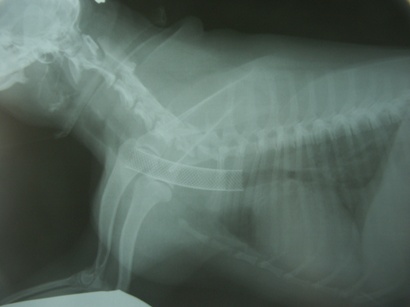

診断 気管虚脱GradeIV(図4)

図4 症例1の初診日。気管陰影ほぼ消失。